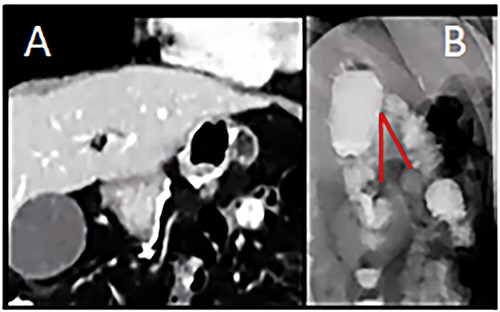

A 29-year-old woman originally from Ecuador’s Amazon region who presented with a history of grade II obesity (body mass index of 37) had undergone bariatric surgery (OAGB) 30 days before admission to our hospital. The patient showed intolerance to a liquid diet and symptoms of reflux starting at the immediate postoperative period, in addition to repeated bilious vomiting after progression to a semisolid diet. Physical examination showed normal vital signs, the abdomen was tender without signs of peritoneal irritation. The protein profile showed alterations with evidence of malnutrition. Abdominal Computed Tomography showed evidence of efferent intestinal loop bending with decreased passage of enteric contrast (Fig. 1A and B). An endoscopy showed stenosis of the gastroenteric anastomosis and obstruction of the efferent loop (Fig. 2).

(A) Computed Tomography: Afferent loop bending and gastroenteric anastomotic stenosis. (B) Radiograph showing distal efferent obstruction.